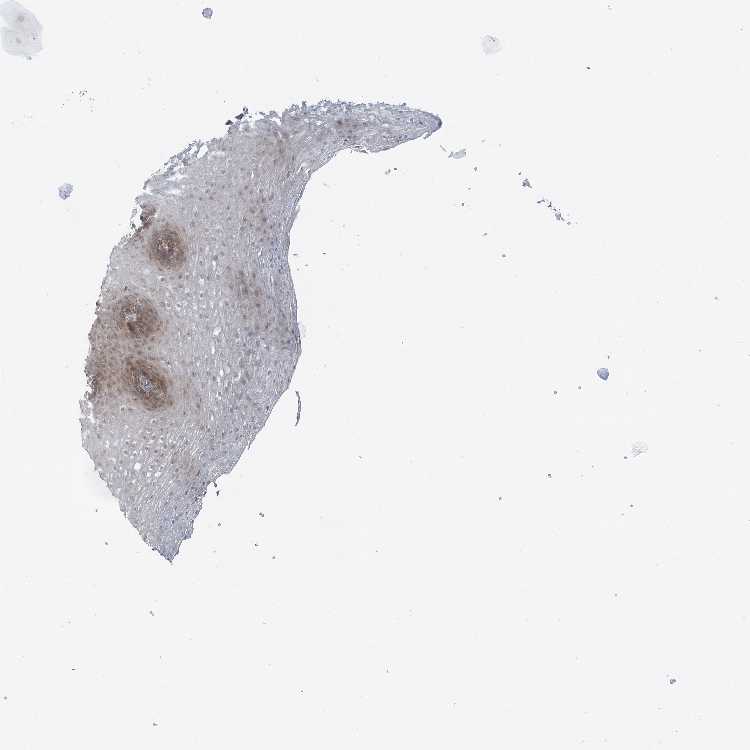

TISSUE PRIMARY DATA ESOPHAGUS Show tissue menu

Esophagus

ESOPHAGUS - Antibody stainingi

Antibody staining in the annotated cell types in the current human tissue is reported as not detected, low, medium, or high, based on conventional immunohistochemistry profiling in selected tissues. This score is based on the combination of the staining intensity and fraction of stained cells.

Each image is clickable and will lead to virtual microscopy that enables deeper exploration of all samples and also displays staining intensity scores, fraction scores and subcellular localization as well as patient and tissue information for each sample.

Antibody HPA030943Antibody HPA030944Antibody HPA030945Antibody CAB034184

Squamous epithelial cells MediumMediumMediumMedium